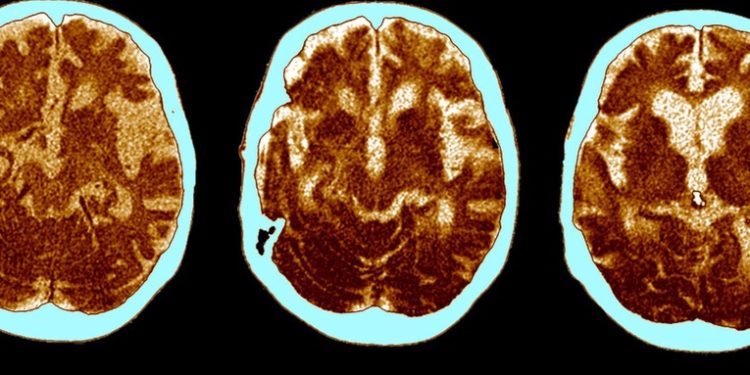

El impacto que tiene sobre la capacidad cognitiva haber sufrido un covid-19 grave es similar al que experimentamos los humanos entre los 50 y los 70 años y equivale a perder 10 puntos de coeficiente intelectual, se afirma en un comunicado emitido por un equipo de científicos de la Universidad de Cambridge y el Imperial College de Londres el 3 de mayo.Los resultados del estudio publicado en la revista eClinicalMedicine de The Lancet muestran que los efectos de la enfermedad se dejan sentir incluso más de seis meses después de terminar la forma aguda y apuntan a que cualquier recuperación es, en el mejor de los casos, gradual.El estudio involucró a 46 pacientes hospitalizados con covid-19 grave, 16 de los cuales requirieron ventilación mecánica durante su estancia hospitalaria.Aproximadamente seis meses después de que terminara la fase aguda de la enfermedad, los participantes se sometieron a una serie de pruebas cognitivas complejas. Cada paciente fue agrupado con 10 controles sanos según su edad y factores demográficos.»El deterioro cognitivo es común a una amplia gama de trastornos neurológicos, incluida la demencia e incluso el envejecimiento rutinario, pero los patrones que vimos, la ´huella digital´ cognitiva del covid-19, han resultado distintos de todos ellos,» comentó el neurocientífico David Menon, de la Universidad de Cambridge, autor principal del estudio.La investigación mostró que los sobrevivientes de coronavirus grave respondían más lentamente a las preguntas y resultaron menos precisos en sus respuestas en comparación con el grupo de control.En particular, los pacientes con covid se desempeñaron especialmente mal en las tareas de analogía verbal, desarrolladas para evaluar ciertas áreas cognitivas y consistentes en encontrar similitudes entre palabras.El estudio encontró que la extensión de estos deterioros cognitivos se correlacionó significativamente con la gravedad de la enfermedad de cada paciente. Los pacientes con covid grave que habían requerido ventiladores en el hospital experimentaron el deterioro cognitivo más significativo. La magnitud de la pérdida resultó similar a los efectos del envejecimiento humano entre los 50 y los 70 años, y equivalente a perder 10 puntos de coeficiente intelectual.Los investigadores barajan varias causas de este deterioro cognitivo y suponen que lo más probable es que se trate de una combinación de factores que, además de una infección viral directa, podrían incluir «el suministro inadecuado de oxígeno o sangre al cerebro, el bloqueo de vasos sanguíneos grandes o pequeños debido a la coagulación y hemorragias microscópicas».Sin embargo, los científicos sugieren que el mecanismo ´destructor´ más importante puede ser el daño causado por la propia respuesta inflamatoria y del sistema inmunológico de las personas afectadas.»Seguimos a algunos pacientes hasta diez meses después de su infección aguda, por lo que pudimos ver una mejora muy lenta», comentó el profesor Menon.

El impacto que tiene sobre la capacidad cognitiva haber sufrido un covid-19 grave es similar al que experimentamos los humanos entre los 50 y los 70 años y equivale a perder 10 puntos de coeficiente intelectual, se afirma en un comunicado emitido por un equipo de científicos de la Universidad de Cambridge y el Imperial College de Londres el 3 de mayo.

Los resultados del estudio publicado en la revista eClinicalMedicine de The Lancet muestran que los efectos de la enfermedad se dejan sentir incluso más de seis meses después de terminar la forma aguda y apuntan a que cualquier recuperación es, en el mejor de los casos, gradual.

El estudio involucró a 46 pacientes hospitalizados con covid-19 grave, 16 de los cuales requirieron ventilación mecánica durante su estancia hospitalaria.

Aproximadamente seis meses después de que terminara la fase aguda de la enfermedad, los participantes se sometieron a una serie de pruebas cognitivas complejas. Cada paciente fue agrupado con 10 controles sanos según su edad y factores demográficos.

«El deterioro cognitivo es común a una amplia gama de trastornos neurológicos, incluida la demencia e incluso el envejecimiento rutinario, pero los patrones que vimos, la ´huella digital´ cognitiva del covid-19, han resultado distintos de todos ellos,» comentó el neurocientífico David Menon, de la Universidad de Cambridge, autor principal del estudio.

La investigación mostró que los sobrevivientes de coronavirus grave respondían más lentamente a las preguntas y resultaron menos precisos en sus respuestas en comparación con el grupo de control.

En particular, los pacientes con covid se desempeñaron especialmente mal en las tareas de analogía verbal, desarrolladas para evaluar ciertas áreas cognitivas y consistentes en encontrar similitudes entre palabras.

El estudio encontró que la extensión de estos deterioros cognitivos se correlacionó significativamente con la gravedad de la enfermedad de cada paciente. Los pacientes con covid grave que habían requerido ventiladores en el hospital experimentaron el deterioro cognitivo más significativo. La magnitud de la pérdida resultó similar a los efectos del envejecimiento humano entre los 50 y los 70 años, y equivalente a perder 10 puntos de coeficiente intelectual.

Los investigadores barajan varias causas de este deterioro cognitivo y suponen que lo más probable es que se trate de una combinación de factores que, además de una infección viral directa, podrían incluir «el suministro inadecuado de oxígeno o sangre al cerebro, el bloqueo de vasos sanguíneos grandes o pequeños debido a la coagulación y hemorragias microscópicas».

Sin embargo, los científicos sugieren que el mecanismo ´destructor´ más importante puede ser el daño causado por la propia respuesta inflamatoria y del sistema inmunológico de las personas afectadas.

«Seguimos a algunos pacientes hasta diez meses después de su infección aguda, por lo que pudimos ver una mejora muy lenta», comentó el profesor Menon.